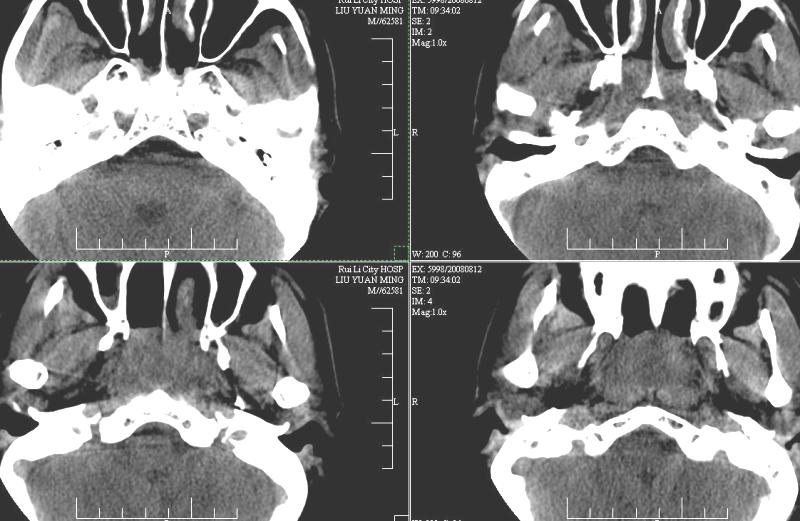

以下是引用ydx_74在2008-8-12 22:09:00的发言:[br]不考虑鼻咽癌。没有淋巴结肿大,没有颅底骨质破坏,咽隐窝、咽鼓管咽口存在,咽旁间隙清楚,平扫ct值34hu,增强动脉期81hu,实质期约85hu,增强幅度达50多,除外增强时机没有掌握好因素,可以考虑鼻咽纤维血管瘤吗?